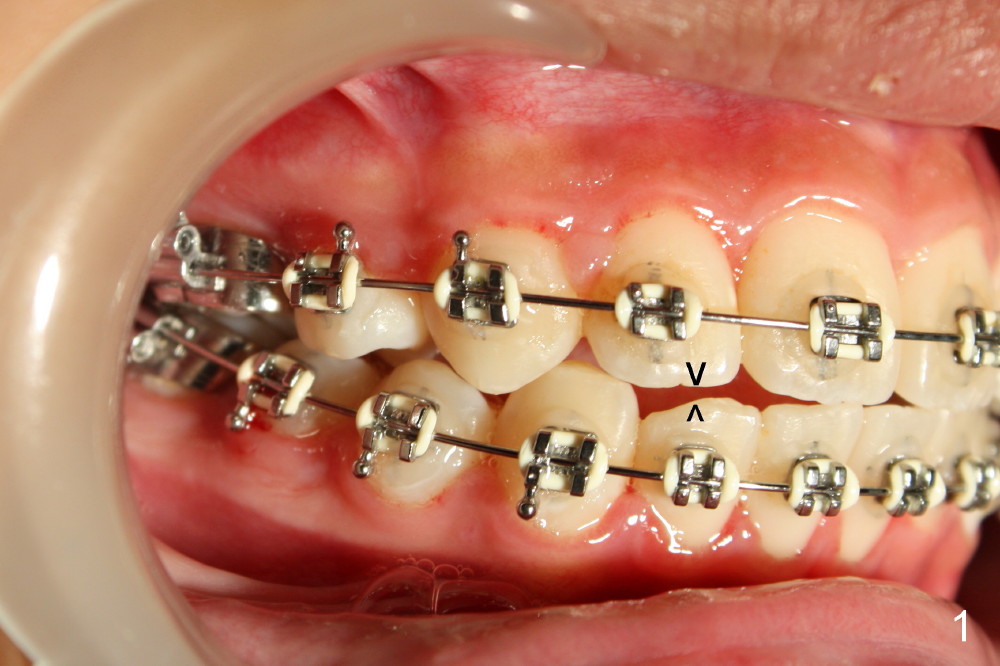

Rebracketing at #6 (Fig.3) leads to resolution of the anterior open bite within a month (Fig.4).